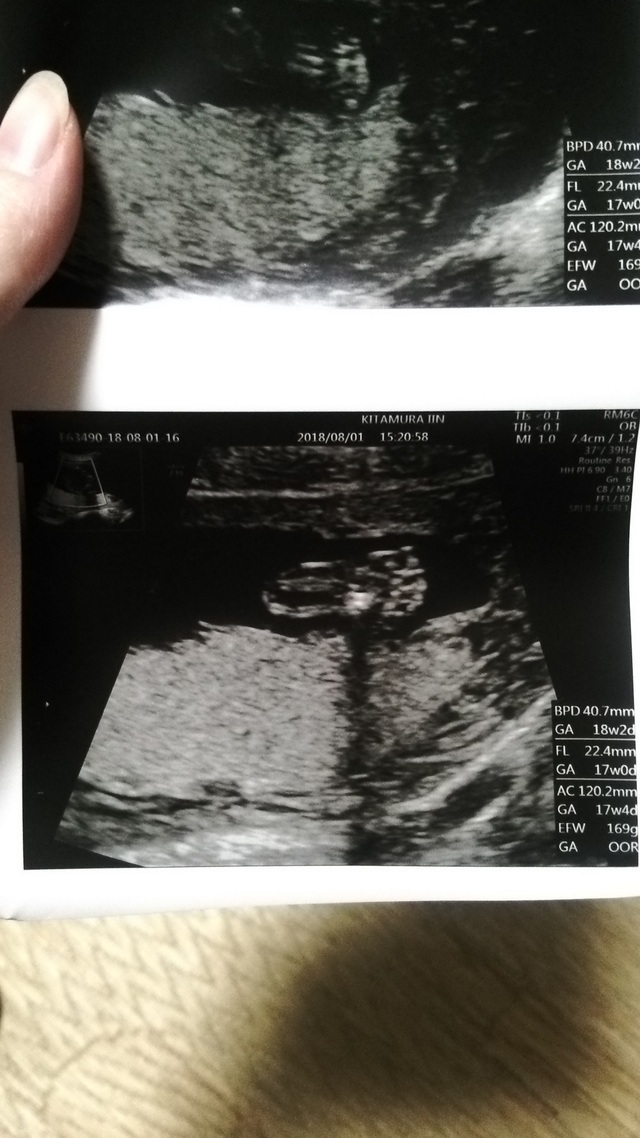

17週4日(17w4d・男の子)|ayu♡ さん(35歳)

エコー写真撮影時のエピソード:

この子の初めての4Dエコーでした。健診が終わって会計待ちの間に、主人にエコーの写メを送りました。

主人は男の子が欲しかったので、ファイティングポーズをしているエコーだったから、男の子に間違いないと!しばらくして主治医からも男の子だろうと言われ、喜んでいた主人を思い出します。